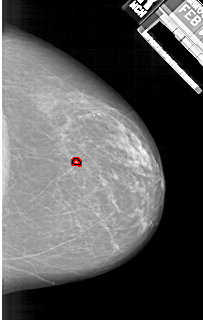

A_1925_1.RIGHT_MLO

RIGHT_CC LINES 5431 PIXELS_PER_LINE 3451 BITS_PER_PIXEL 12 RESOLUTION 43.5 OVERLAY

FILE: A_1925_1.RIGHT_CC.OVERLAY

TOTAL_ABNORMALITIES 1

ABNORMALITY 1

LESION_TYPE CALCIFICATION TYPE PLEOMORPHIC DISTRIBUTION CLUSTERED

ASSESSMENT 4

SUBTLETY 3

PATHOLOGY BENIGN

TOTAL_OUTLINES 1

BOUNDARY